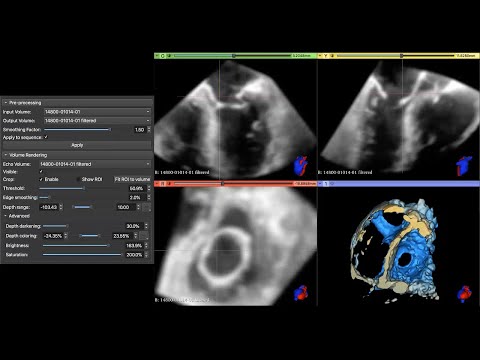

👌Embarking on a mission to become more familiar with creating #3Dprint in @3DSlicerApp ! Example of 🫀 from a simple threshold and then using the remove islands and smooth function to optimize. #yesCCT @mmamas1973 @iamritu @purviparwani @tiffchenMD @KidsAtColumbia @ColumbiaMed

We are thrilled to publish our description of #SlicerHeart, a open source, cardiac-focused image processing extension for @3DSlicerApp that has now been downloaded over 44,000 times. frontiersin.org/articles/10.33…